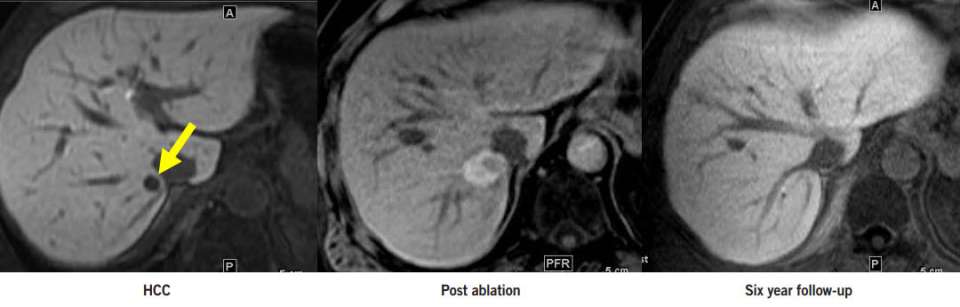

Hepatocellular carcinoma (HCC) is the most common type of primary liver cancer. Primary liver cancer refers to cancer that originates in the liver rather than cancers from other organs that metastasize to the liver (see metastatic liver cancer). HCC can start as a single tumor or as several tumor nodules across the liver.

Our physicians are liver specialists in both imaging and minimal invasive therapy. They work in collaboration with the liver surgeons, hepatologists, and liver oncologists to offer treatments either alone or in combination with traditional surgical and medical therapies. Treatment strategy is personalized taking into account individual risk factors and very importantly, the precise extent of tumor and the condition of the underlying liver through imaging assessment. Optimal strategy may include one or a combination of minimal invasive treatments below:

- Thermal ablation (microwave and radiofrequency)